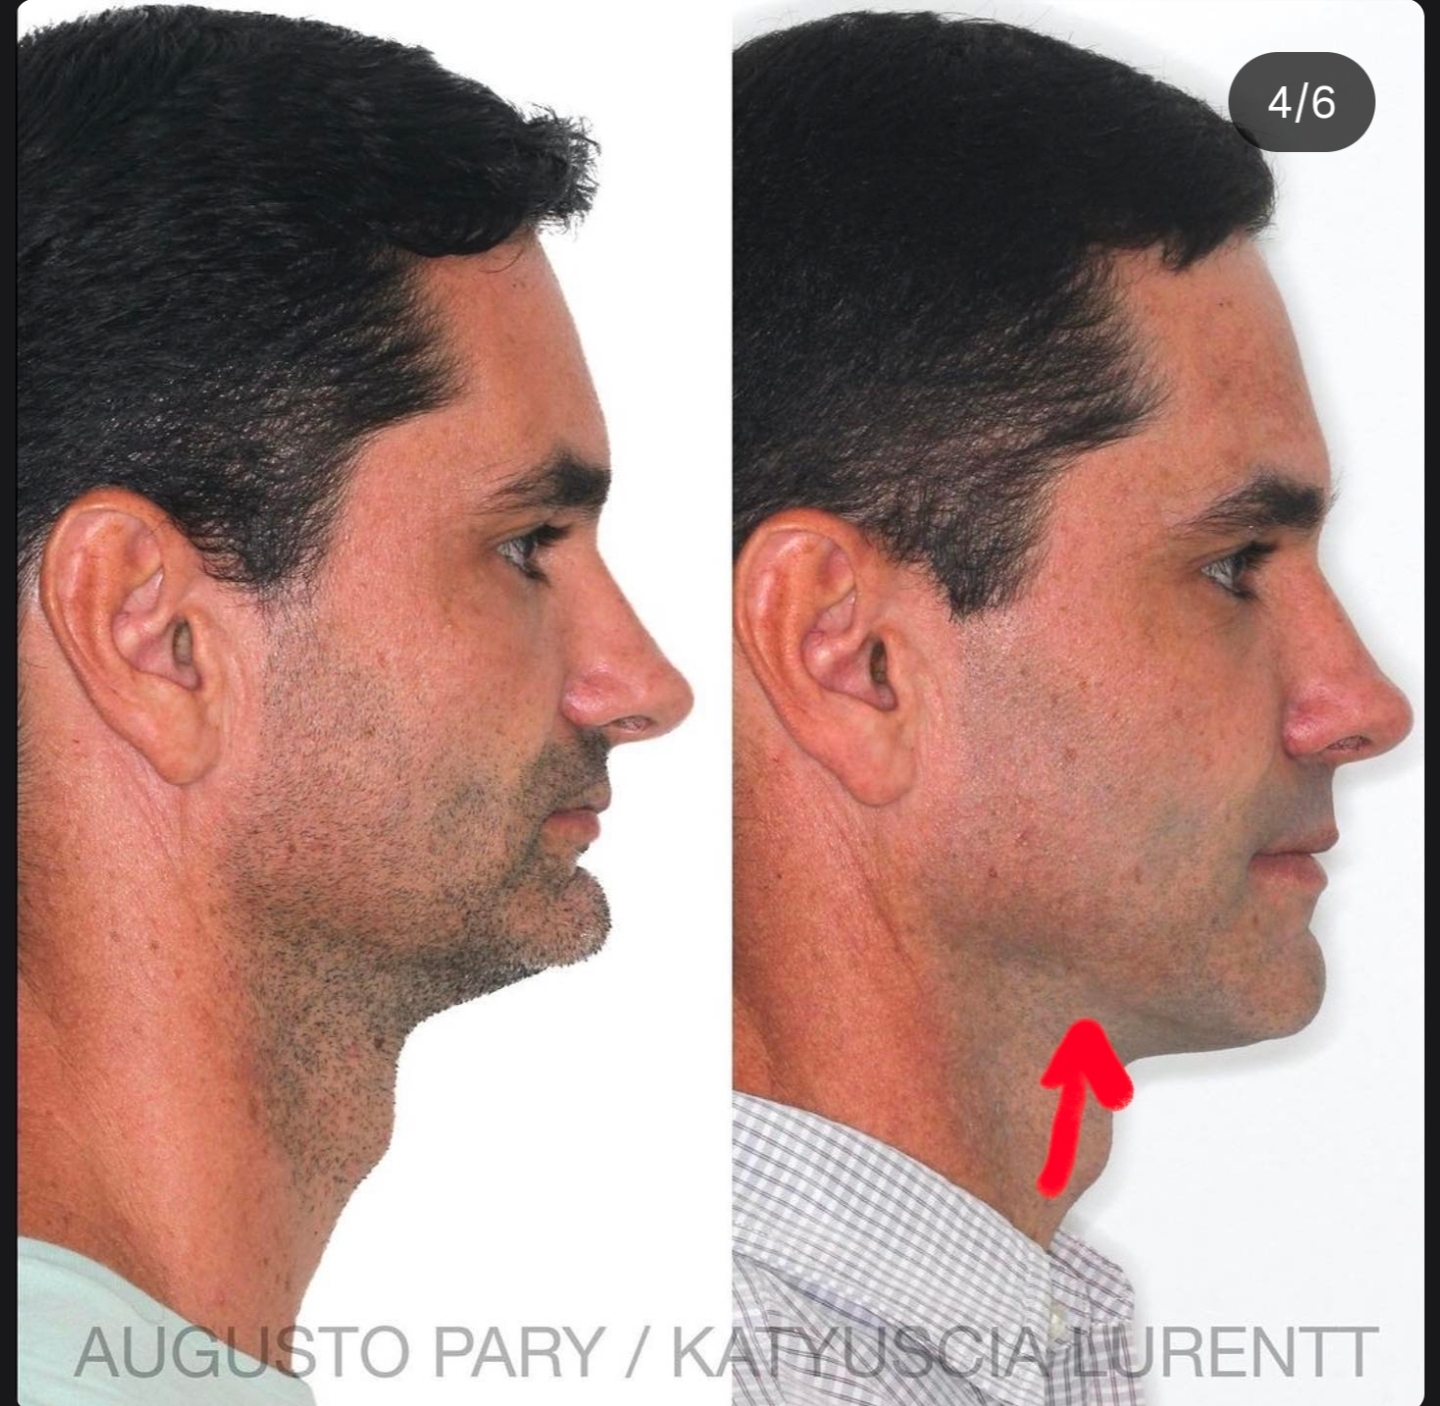

more no bonegraft huge genio from ram

more no bonegraft huge genio from ram